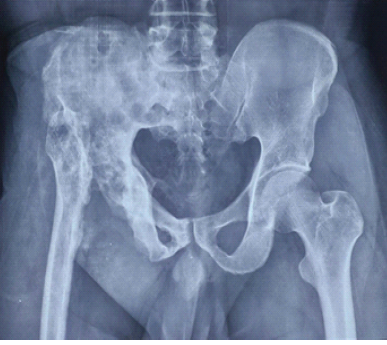

A Primary Hyperparathyroidism in an Adolescent Female with Pathological Fractures and Multiple Bone Lesions Due to Parathyroid Adenoma: Case Report

Harsh Pratap Singh , Chetan Singh , Kishore Parihar , Ankita Parmar , Sanavvar Ali , Anmol Chaurasia

………………………………p.146-151